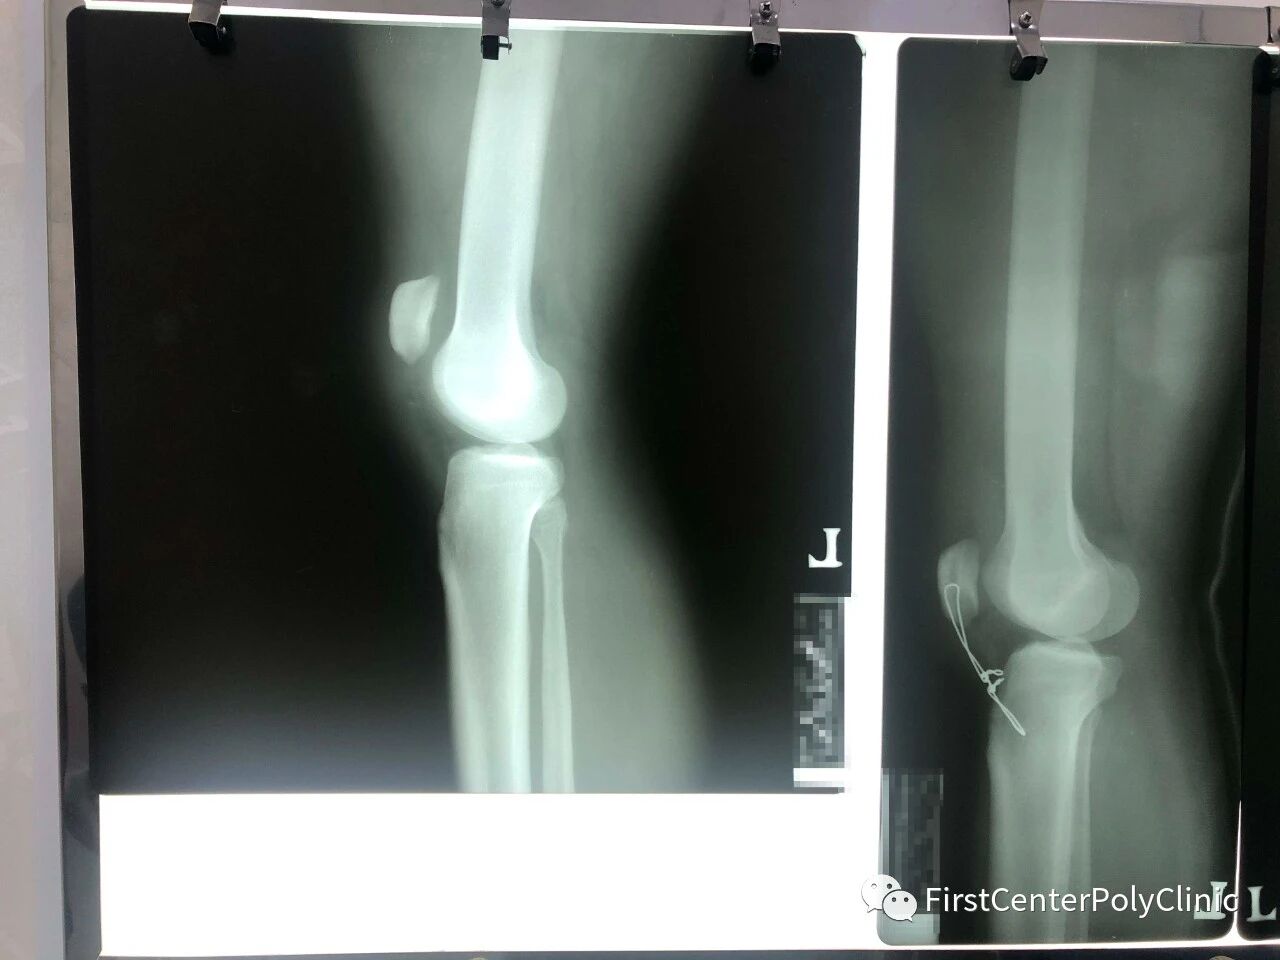

患者自述在运动中用力过猛,把膝盖扭了,由于患者由暹粒转院至金边,看着患者腿上重重的石膏,我们发觉此事并不简单,在安抚患者的同时,安排拍片检查,结果发现髌骨明显上移,膝关节肿大,医生会诊后,最终诊断为髌韧带断裂。由于髌韧带起着“承上启下”的作用,如不及时恢复,将来会影响正常的行动。

外科院长当机立断决定手术,在三名主任医师2个多小时的共同努力下,手术顺利完成。通过X光片可以看到,髌骨回归原位,并且在韧带断裂上下方进行了减张固定,以便韧带更好的生长愈合,同时也可以使膝关节尽早恢复功能。